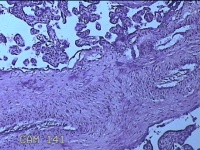

胎盘组织

性别

女

年龄

30岁

临床诊断

妊娠合并中度贫血

一般病史

停经39+2周,B超检查发现羊水偏少6小时。

标本名称

大体所见

灰白暗红色胎盘组织16.5x14.5x3.5㎝一个,表面光滑,血管突出,颜色发暗,绒毛面结节状,有轻度糜烂,暗红色,有少许凝血块,切面见绒毛内有暗红色血液渗出,边缘蜕膜可见多个小血肿,脐带39x1.8x0.3㎝,螺旋状扭曲,切断脐带,见脐血管内有凝血块。